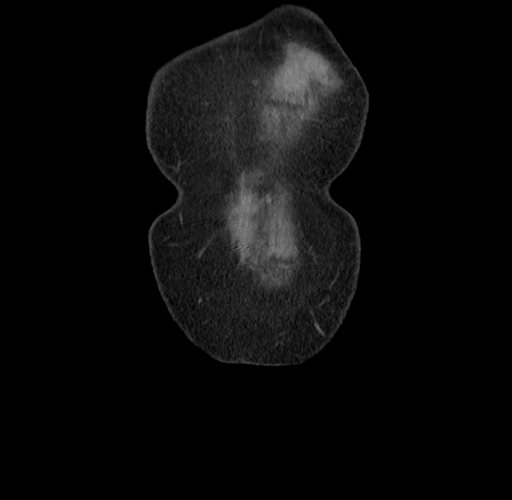

MRI T1